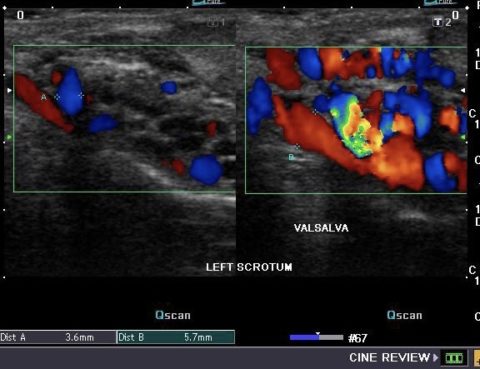

Κιρσοκήλη ονομάζεται η ελικοειδής διάταση των φλεβών του όρχεως και πρόκειται για φλεβική ανεπάρκεια, όπως οι κιρσοί στα πόδια. Συνήθως, πιο συχνά παρατηρείται στον αριστερό όρχι και αυτό οφείλεται σε ανατομικούς λόγους Υπό φυσιολογικές συνθήκες, οι φλέβες επιτρέπουν την κίνηση του αίματος από την περιφέρεια του σώματος προς το κέντρο και από τις μικρότερες προς…